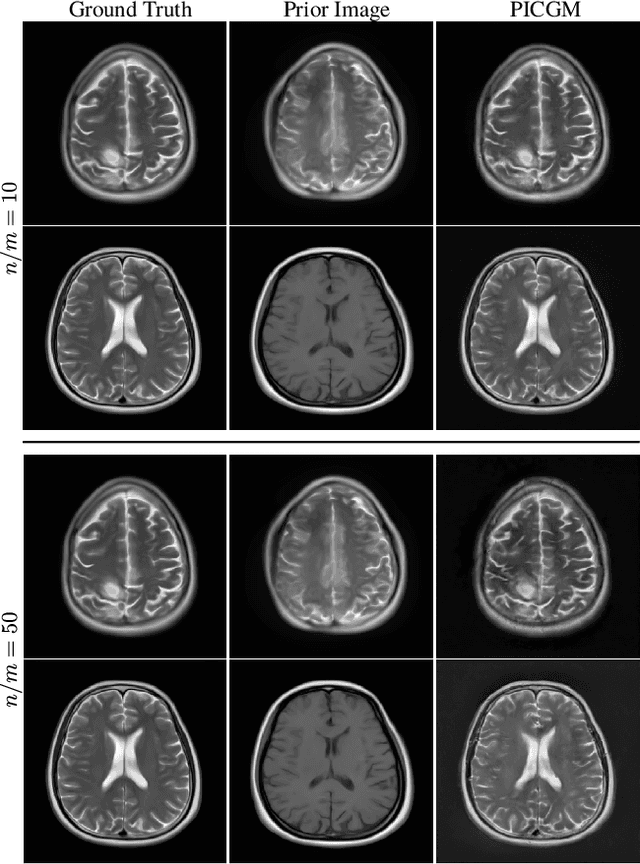

Abstract:Computed medical imaging systems require a computational reconstruction procedure for image formation. In order to recover a useful estimate of the object to-be-imaged when the recorded measurements are incomplete, prior knowledge about the nature of object must be utilized. In order to improve the conditioning of an ill-posed imaging inverse problem, deep learning approaches are being actively investigated for better representing object priors and constraints. This work proposes to use a style-based generative adversarial network (StyleGAN) to constrain an image reconstruction problem in the case where additional information in the form of a prior image of the sought-after object is available. An optimization problem is formulated in the intermediate latent-space of a StyleGAN, that is disentangled with respect to meaningful image attributes or "styles", such as the contrast used in magnetic resonance imaging (MRI). Discrepancy between the sought-after and prior images is measured in the disentangled latent-space, and is used to regularize the inverse problem in the form of constraints on specific styles of the disentangled latent-space. A stylized numerical study inspired by MR imaging is designed, where the sought-after and the prior image are structurally similar, but belong to different contrast mechanisms. The presented numerical studies demonstrate the superiority of the proposed approach as compared to classical approaches in the form of traditional metrics.

Abstract:Obtaining an accurate and reliable estimate of an object from highly incomplete imaging measurements remains a holy grail of imaging science. Deep learning methods have shown promise in learning object priors or constraints to improve the conditioning of an ill-posed imaging inverse problem. In this study, a framework for estimating an object of interest that is semantically related to a known prior image, is proposed. An optimization problem is formulated in the disentangled latent space of a style-based generative model, and semantically meaningful constraints are imposed using the disentangled latent representation of the prior image. Stable recovery from incomplete measurements with the help of a prior image is theoretically analyzed. Numerical experiments demonstrating the superior performance of our approach as compared to related methods are presented.